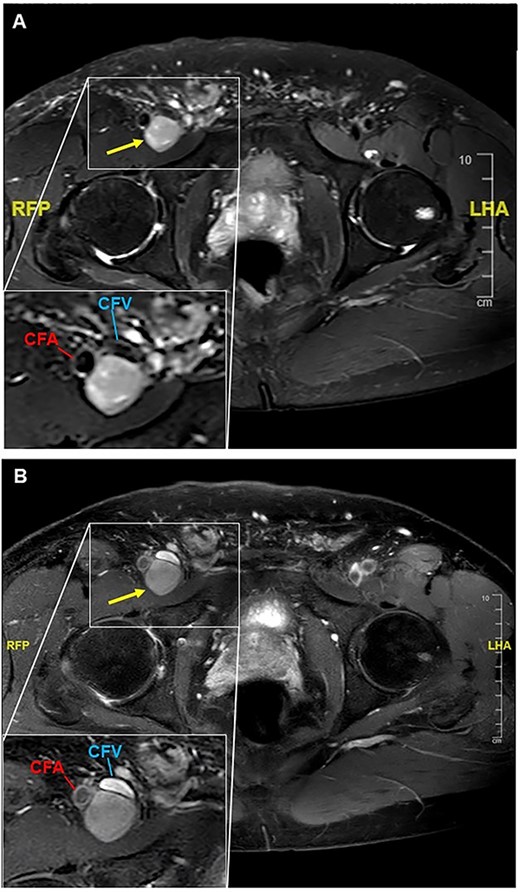

To clarify the entity of the lesion, MRI-Imaging and a fine needle biopsy were performed. In the MRI, the tumor had a slightly hyperintense signal in the T2-weighted images and a more hypointense signal compared to fat. In the T1-weighted images, the signal of the tumor was comparable to the muscular signal, and after application of contrast medium, a slight enhancement of the tumor was observed (Fig. 2). In the fine needle biopsy, proliferating cells were seen, but no conclusive histological diagnosis could be made.

T1-weighted MR-images of the right groin are presented pre- (A) and post-application of contrast medium (B). (A) A tumor with a diameter of 26 × 24 × 54 mm is seen dorsal to the common femoral vein and artery. In the left lower corner, a magnification of the area of interest is shown. CFV = common femoral vein; CFA = common femoral artery. (B) Addition of contrast displays the compression of the common femoral vein, but no flow impairment is seen. In the left lower corner, a magnification of the tumor is presented.